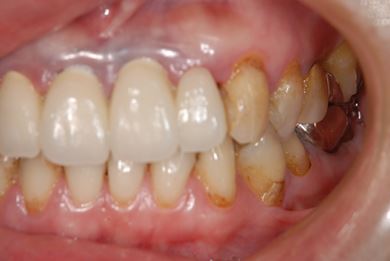

インプラント治療+セラミック治療

| 性別/年齢 | 女性 / 47歳 | ||||||||||||||||||||||||||||||||

| 主訴 | 前歯の黄ばみが気になる。 | ||||||||||||||||||||||||||||||||

| 治療方針 | インプラント・セラミック治療にて、機能的・審美的回復を行う。 | ||||||||||||||||||||||||||||||||

| 治療内容 | インプラント3本、ジルコニアフレームオールセラミッククラウン7本(ジルコニア用土台1本)、メタルボンドセラミッククラウン3本(メタルボンド用土台3本)、ハイブリッドセラミッククラウン3本、ハイブリッドセラミックインレー3本 | ||||||||||||||||||||||||||||||||